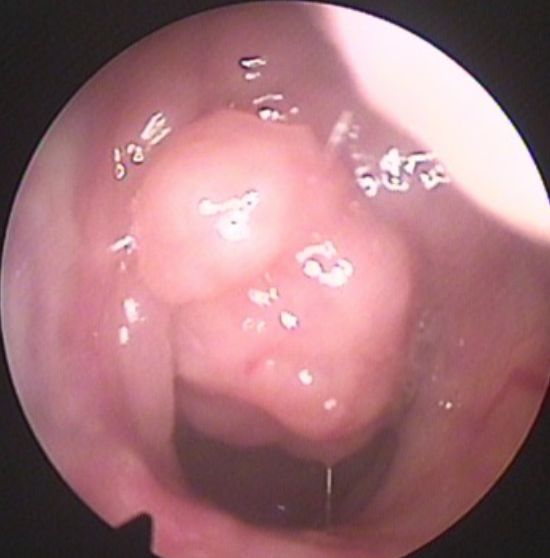

鼻咽镜检查:使用一个带摄像头的内镜经鼻伸入,直接观察腺样体堵塞后鼻孔的程度:

◉25%及以下:I度

◉26%-50%:II度

◉51%-75%:III度

◉76%-100%:IV度

通常III度以上且伴有临床症状的,考虑诊断为腺样体病理性肥大。

▲腺样体无肥大